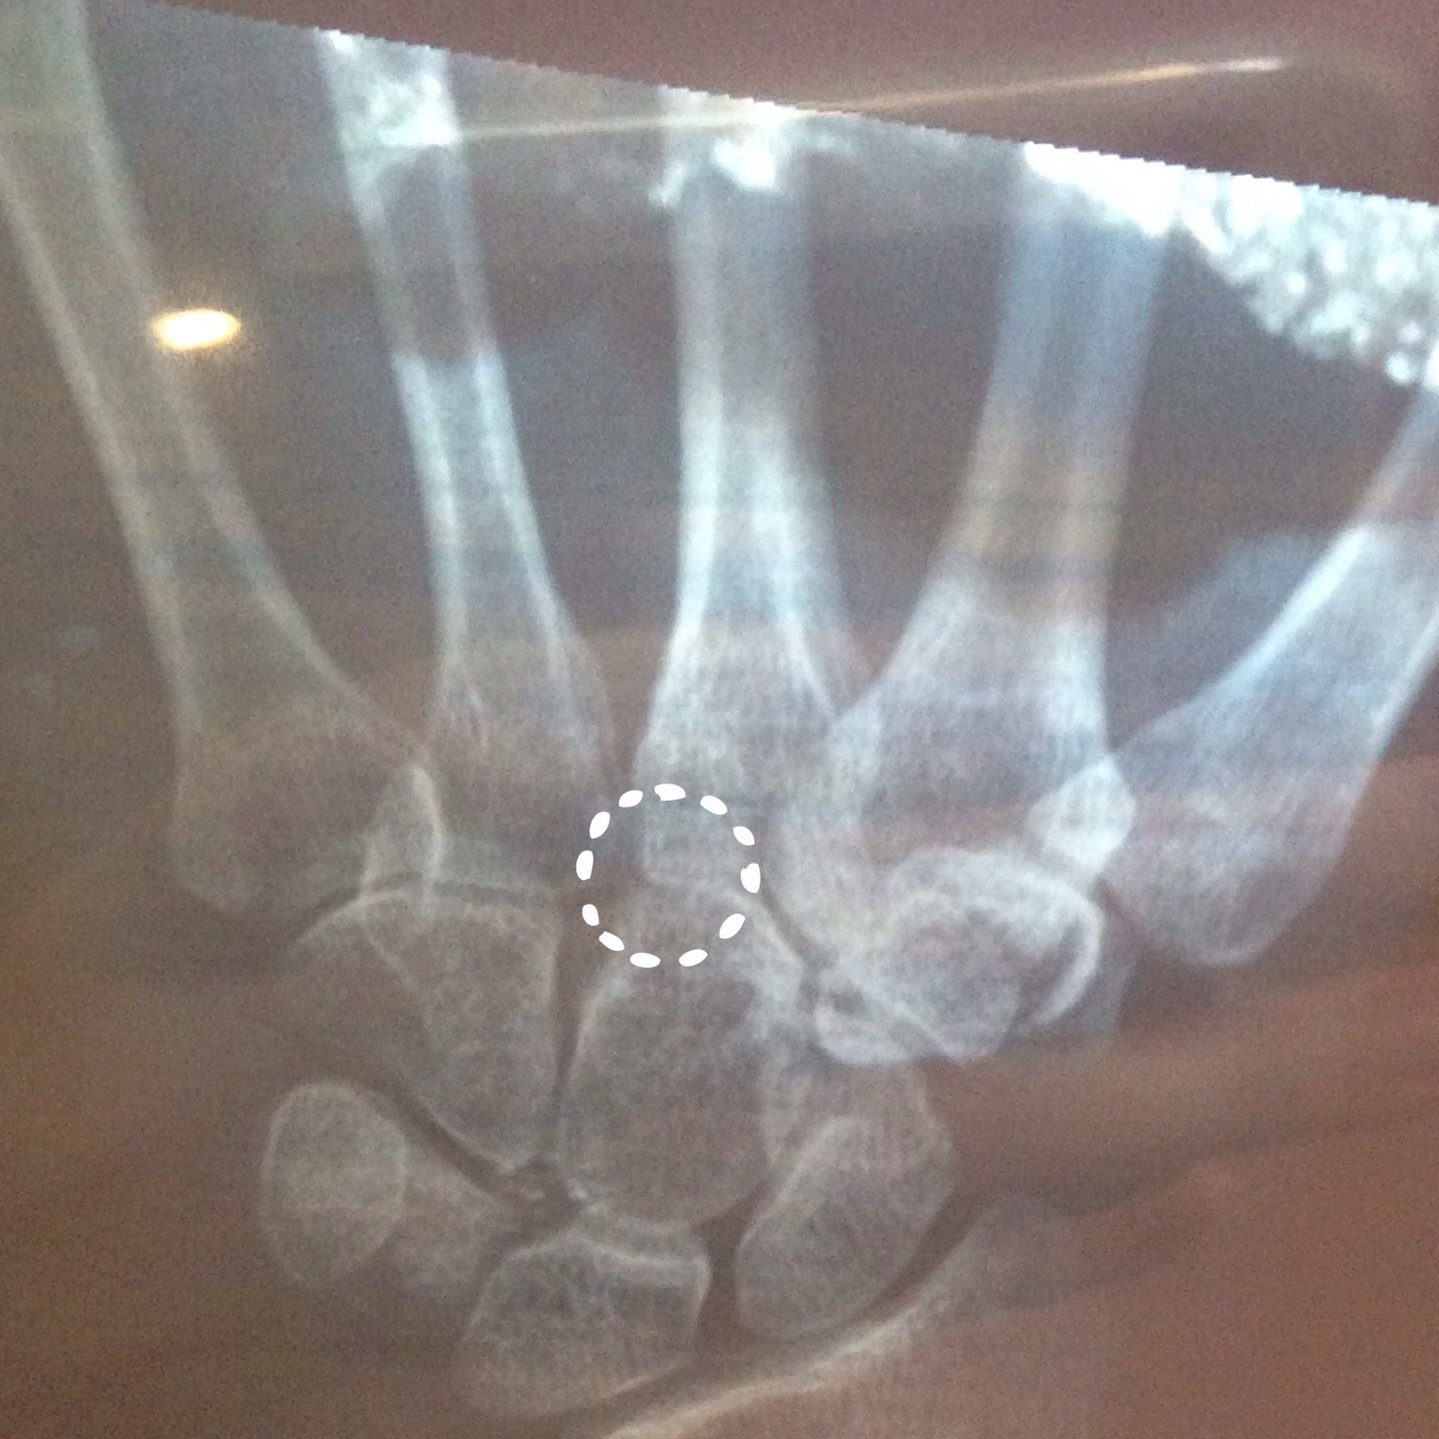

Now it is December and the pain is worse than ever. My dominant hand is pretty close to useless and if it isn’t heavily braced, cracks and crunches like a bag of Corn Flakes under a rolling truck tyre. Needless to say, I’ve seen a few doctors and had a good dollop of radiation blasted through it in search of the problem.

My remaining option is surgery. The procedure will fuse the pained joint and stop the bones rubbing against one another. And while the idea of preventing the bones grinding away at each other, gluing or welding them together sounds just about as appealing as a bath full of angry scorpions on a hot day. I’m assured my use of the appendage will return and typing and writing will be easy and pain free, but…